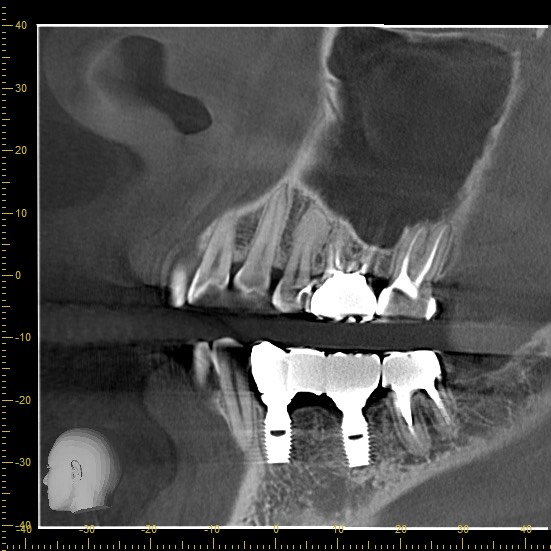

Імплантація